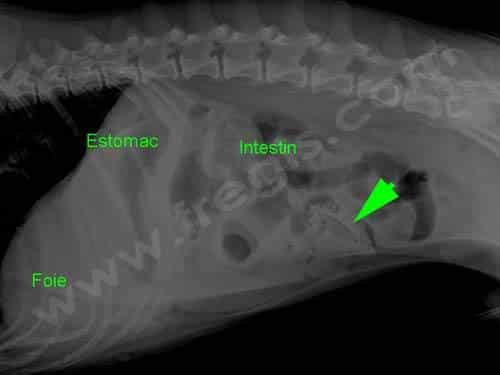

Radiographie de l’abdomen (ventre) d’un chien ayant avalé un noyau de pêche et présentant des vomissements. Il y a ici occlusion digestive

Le vomissement est un symptôme peu spécifique et commun à de très nombreuses maladies ou situations : maladies infectieuses, intoxications alimentaires, maladies métaboliques (diabète sucré, insuffisance rénale, insuffisance surrénalienne, …), ingestion de produits toxiques, effets secondaires de nombreux médicaments, occlusions digestives, certains cancers (en particulier digestifs), maladies neurologiques, …

Dans les autres cas, le recours à un service d’urgence est conseillé, voire indispensable dans les situations les plus sérieuses (et notamment si le chien tente de vomir sans y parvenir). Une surveillance vétérinaire, des examens complémentaires (radiographies, analyses,…), des perfusions prolongées pour réhydrater l’animal,… sont souvent nécessaires.

Hospitalisation

Souvent nécessaire et même indispensable dans les situations les plus graves. Dans certains cas, une fibroscopie digestive, voire une intervention chirurgicale d’urgence, peuvent même être indispensables, notamment en cas d’ingestion de corps étranger, d’occlusion intestinale, …